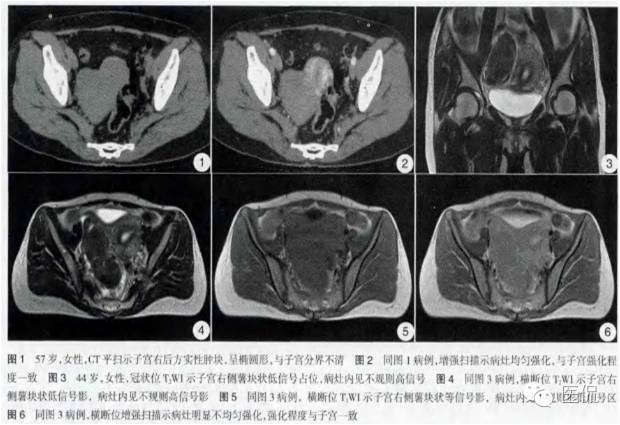

女,57岁;

五天前开始感觉下腹胀痛,为持续性,自服“左氧氟沙星”治疗,疼痛稍有缓解。无阴道流血,外院B超提示:盆腔不均回声包块约10cm,边界清,形态规则。

子宫前方可及一直径10cm左右实性占位,活动差,轻压痛。

◆为单发肿瘤,表现为盆腔内实性肿块,囊性区较小;境界较清楚;肿瘤体积一般较大

◆CT表现:平扫呈等或稍低密度肿块,低于子宫肌层,可伴少量低密度囊变区,无壁结节

◆MRI表现:实性成分T1WI为稍低信号,T2WI纤维部分表现为低信号,囊变区为高信号。

◆增强肿瘤实性成分呈轻-中度不均匀延迟强化,明显弱于子宫肌层;也可无强化